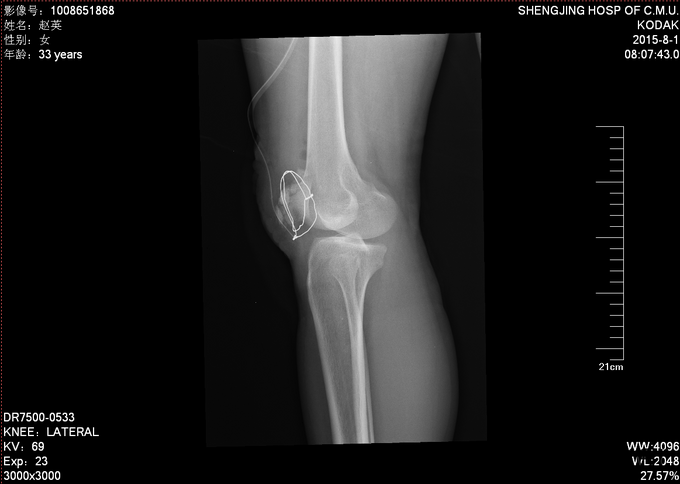

入院后完善检查,患者创口换药,观察患者创口变化,于一周后无红肿渗出后,无发烧发热后。查无手术禁忌症后行右髌骨骨折切开复位张力带内固定术